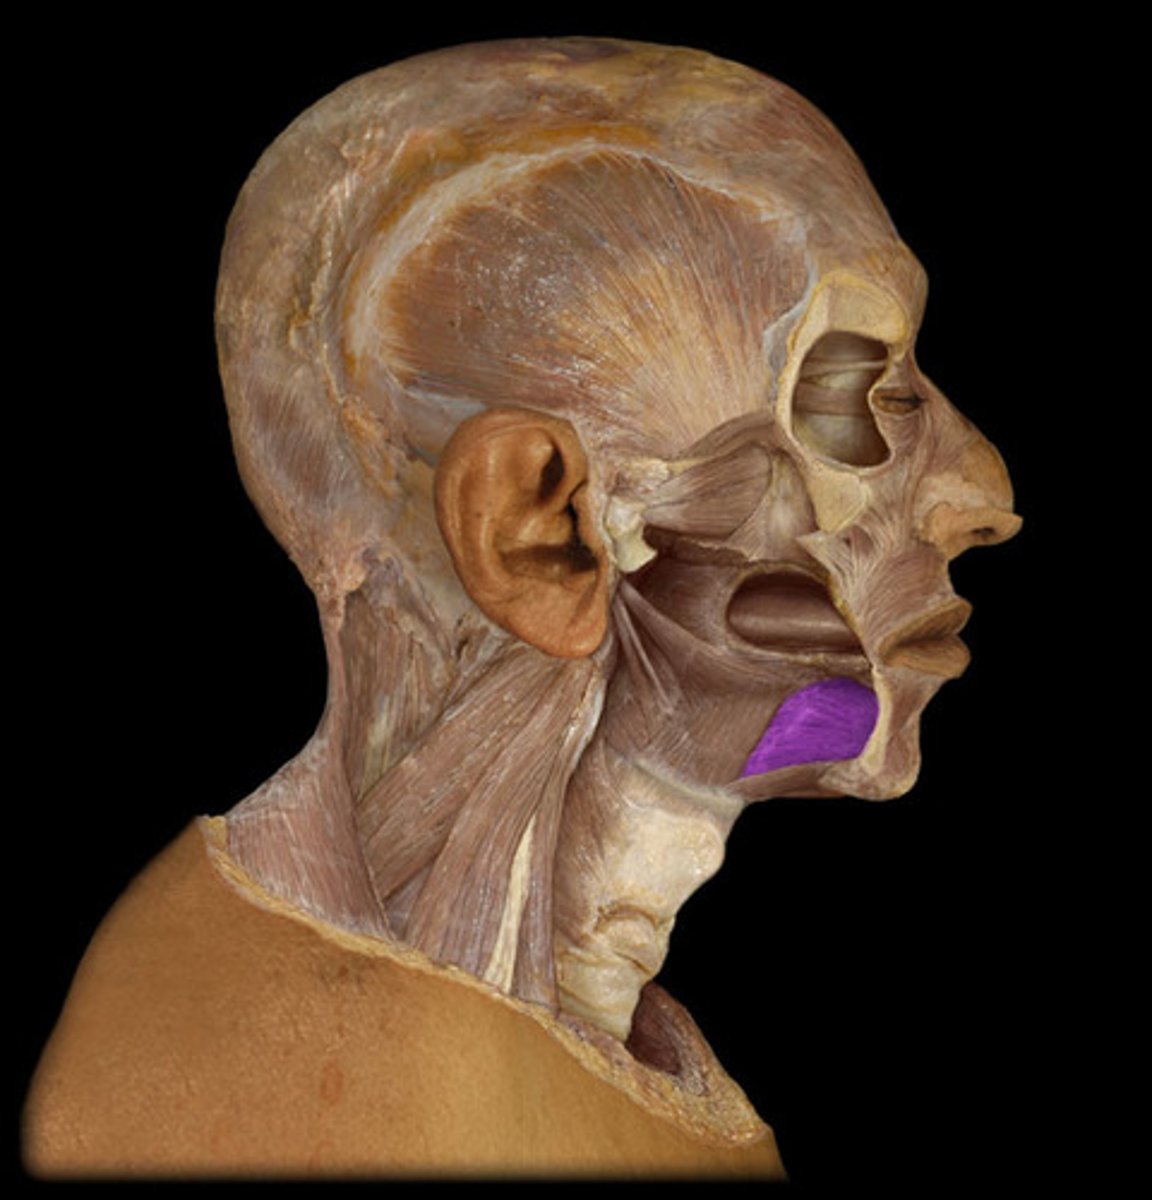

Medial pterygoid